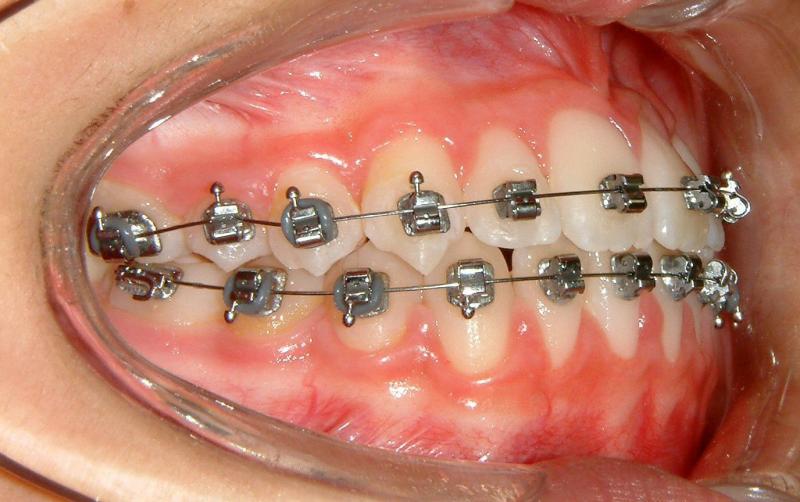

Case 4: 12 yr-old female (without extraction)

Fig. 9 View shows negative overjet and ectopic UL canine (initial)

© Copyright 2007, Vu Orthodontics. All rights reserved.

Fig. 10 View shows progress (11 months)